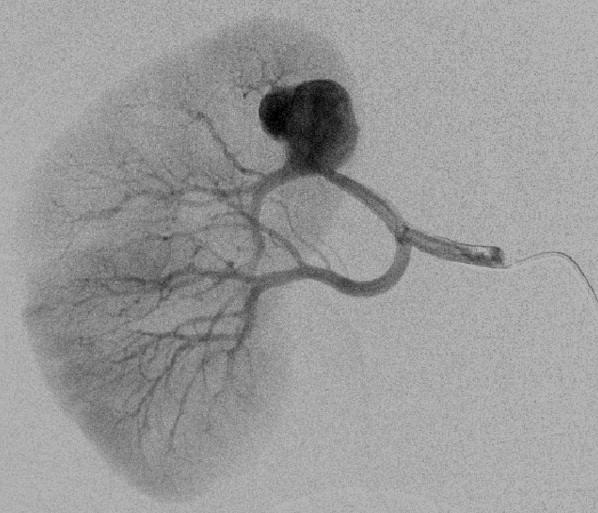

末端动脉阻塞(end-artery occlusion)

末端动脉栓塞:医源性肾损伤-移植肾活检

活检后动脉瘤破裂 |

微导管在载瘤动脉末端 |

载瘤动脉末端栓塞 |

Coil=3 |

直接动脉末端栓塞的过程是简单推出弹簧栓子(simply pushed out coil),但要求弹簧栓子的直径≥血管直径